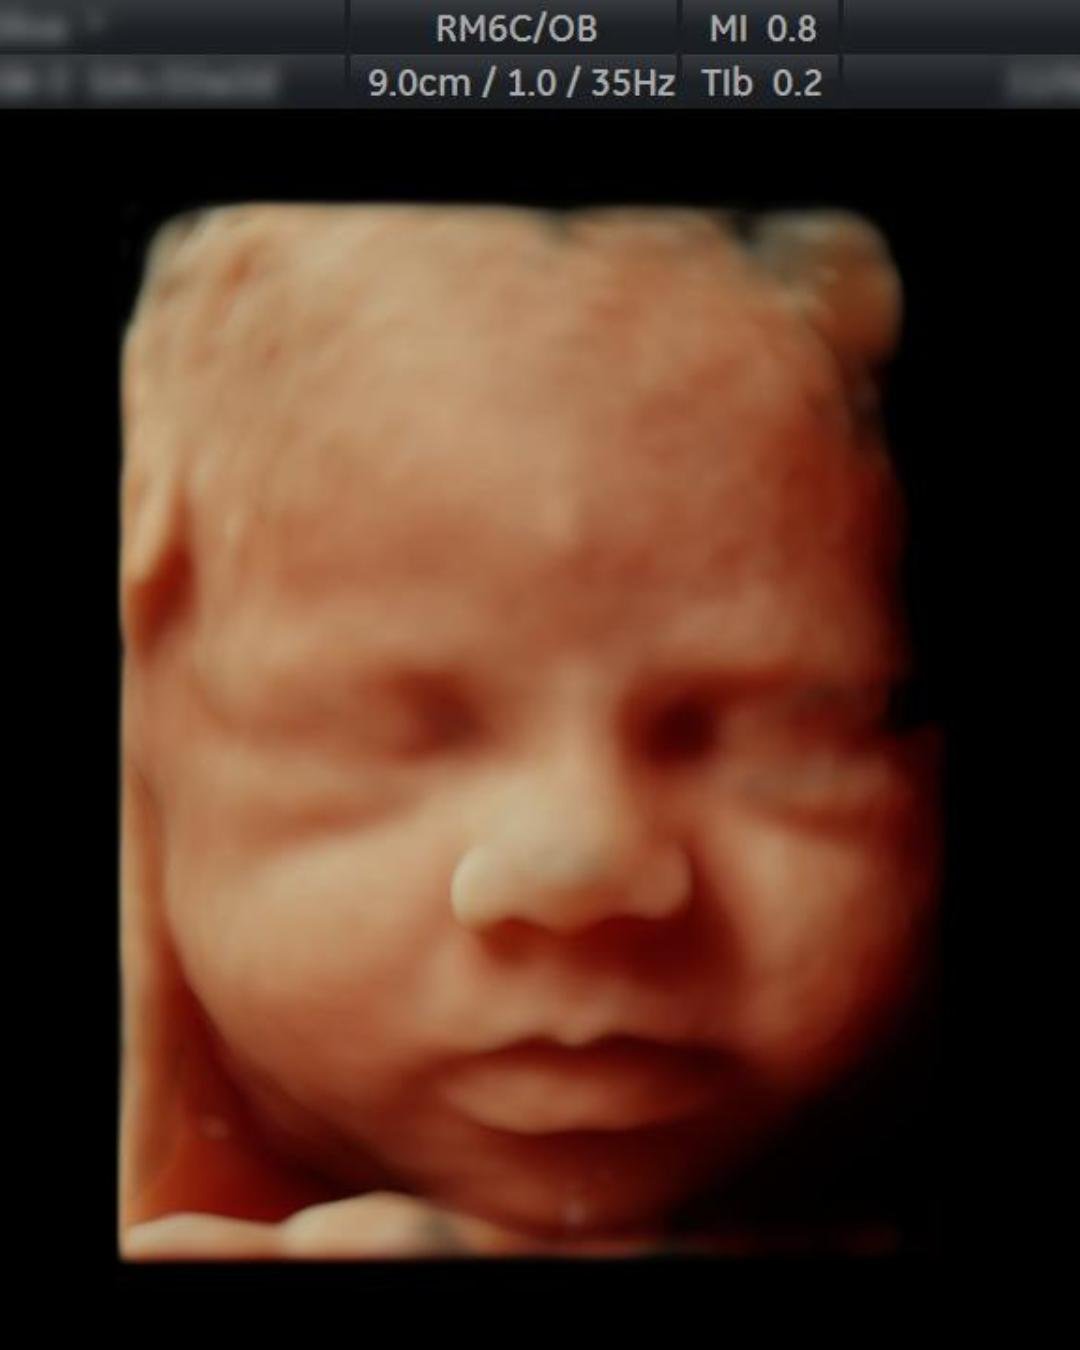

image Ultrasound 3D 4D of baby in mother's womb.

ULTRASONIDO ESTRUCTURAL GENÉTICO

Revisión detallada de todo el cuerpo y circulación de tu bebé para poder descartar síndromes o anormalidades.

Se evalúa:

• Ideal para la búsqueda de anormalidades fetales

• Cuerpo completo del bebé

• Corazón y circulación

• Cerebro y desarrollo neurológico

• Placenta y flujo sanguíneo

• Incluye 4 y 5D

Se recomienda un ultrasonido estructural por cada trimestre del embarazo.

Timing recomendado: 11-14 semanas, 20-24 semanas y 30-32 semanas

Valoración

$3,000 pesos